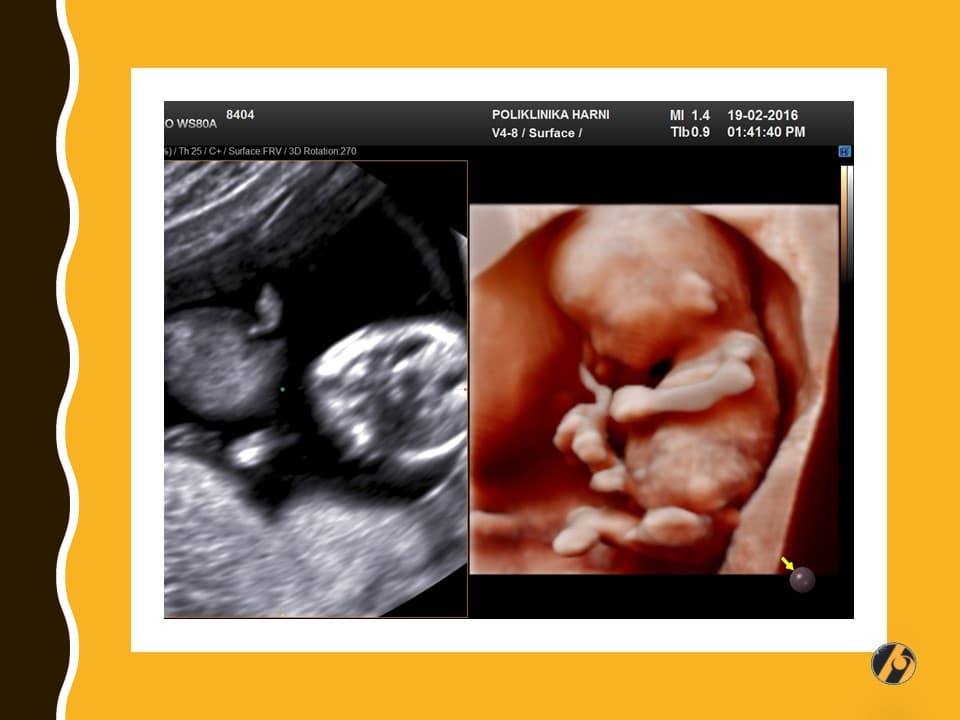

Lice vaše bebe sve je razvijenije. Prepoznaju se korijen nosa, formirani su obrazi, uši su sa strana na vratu prema glavi, a oči su sve bliže jedno drugome. Štitna žlijezda dovršila je svoj razvitak i spremna je za početak stvaranja vlastitih hormona.

Lanugo dlačice otpadaju, a vernix većim dijelom iščezava prije nego što će se beba roditi. Zajedno s lanugo dlačicama pokazuju se obrve, za sada veoma nejasno, čak niče i po koja vlas na glavi. Mišići lica se počinju kontrahirati, pa se nalicu mogu vidjeti grimase i zijevanje. Ispod zatvorenih očnih kapaka počinju se pokretati oči.

Vaša beba dugačka je 8.0 - 11.0 cm, a teška 30 - 60 g.